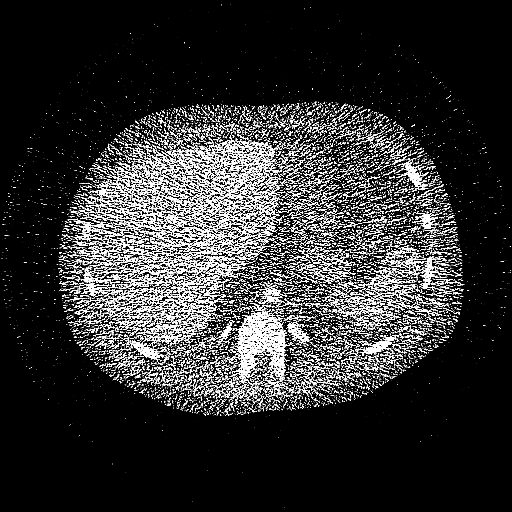

Reconstructed 35 – 85 keV Mono-Energetic Images

(digital human)